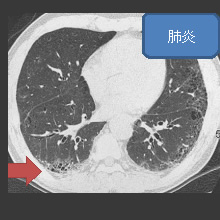

CTとはコンピュータ断層撮影のことで、X線を使用して胸部を輪切りの状態で撮影する検査です。

胸部単純X線撮影では見えにくい、心臓の陰に隠れた病変や小さな病変まで撮影することができます。

肺がんや肺炎、肺気腫などの診断に有用です。

- 肺炎